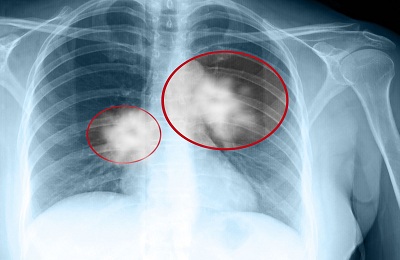

Рентгенограмма используется для выявления разнообразных патологических заболеваний легких, с ее помощью можно выявить различные новообразования в легких. На рентгене новообразование просматривается как нечеткая тень с очерченными границами, структура таких образований достаточно четкая и однородная, однако можно заметить и некоторые особенно выделяющиеся элементы: похожие на глыбы небольшого размера обезвествления – гамартомы и туберкулемы – и твердые, структурно похожие на кость, фрагменты – тератомы.

Новообразования доброкачественной или злокачественной природы нередко проходят бессимптомно – пациент не предъявляет никаких жалоб, а данные патологии возможно обнаружить лишь на исследованиях с использованием рентгена.

Но все же нужно знать, что приведенные выше сведения не дают стопроцентной гарантии доброкачественности опухоли и, безусловно, не могут служить достаточным основанием для постановления диагноза. Только специалист, наблюдающий длительное время пациента и знающий его историю болезни, на основе анализа данных и рентгенограммы, а также эндоскопических наблюдений может сделать экспертное заключение. Решающим моментом является биопсия, изучение материалов которой станет основанием для вердикта врача.

Важным моментом станет сохранение старых рентген-снимков, которые нужны для того, чтобы сравнить с новейшими снимками. Это позволит более точно идентифицировать локализацию новообразования и определить его природу. Эта операция поможет сохранить время и избежать ненужных действий и скорее приступить к лечению.